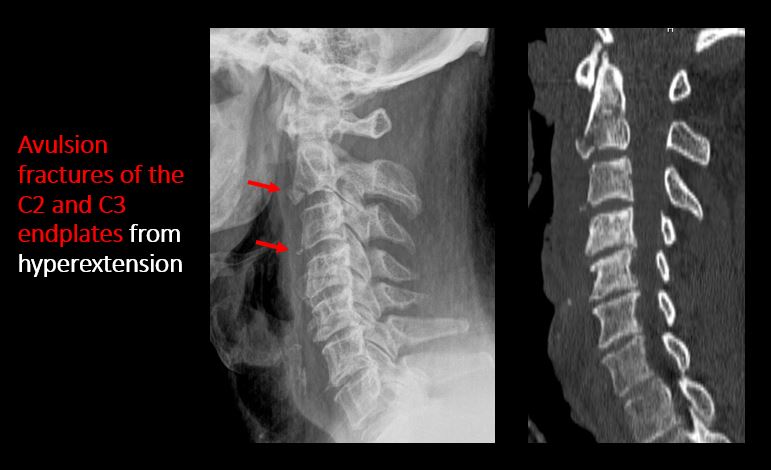

There is a fracture or distraction of a C3-T1 vertebral body, transverse or spinous process, or other posterior element. |

Yes | NA |

There is evidence of an end plate avulsion or other fracture. |

No | NA |

Limited flexion and extension views show evidence of ligamentous injury at C5-C6 with kyphotic deformity, bilateral perched facets, and rotational deformity. Mild anterior wedging of C5 is likely chronic.